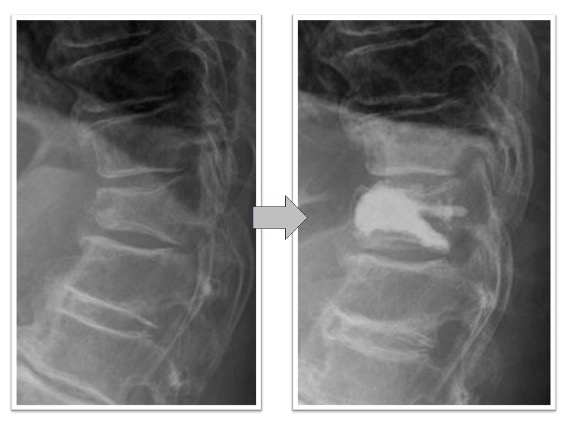

腰椎固定術実例(OLIF症例、*患者様の許可を得て掲載しています)

椎間板ヘルニア(図1)

体動困難を伴う激烈な下肢痛に対してL4/5の固定術を実施。術前に認められていたL4/5の椎間板ヘルニアがOLIFによる固定術後、間接除圧効果などによって消失しています(図1、赤丸)。レントゲンでは椎間ケージと腰椎L4とL5を固定する椎弓根スクリューが確認できます(図1、下段)。本症例の傷は左わき腹に4-5cmと、背部のスクリュー刺入部位に2㎝弱の傷が4つとなります。術後、痛みは消失しました。

図1